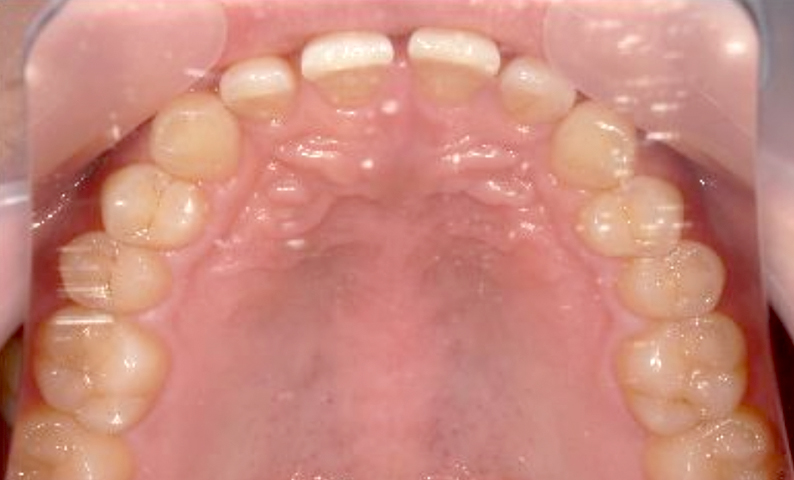

| 治療前 | 治療後 |

|---|---|

|